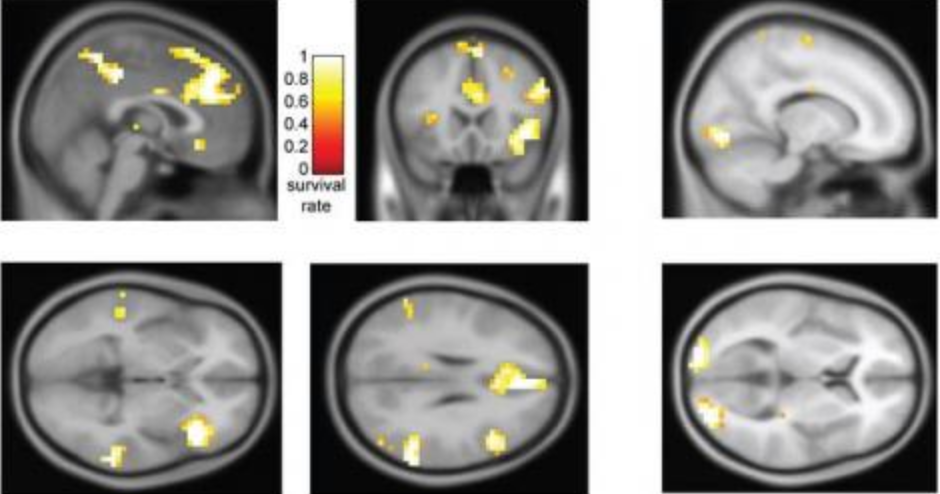

악의적 범죄자(왼쪽)와 과실범(오른쪽)의 뇌 영상 차이

자기공명영상장치 fMRI와 머신러닝을 이용한 인공지능의 발달로 뇌 영상 촬영 결과를 분석해, 범죄자의 죄질과 고의성을 구분할 수 있는 기술이 발전했다. 뇌 영상 자료를 확대 수집하여 빅데이터를 구성한다면, 뇌 영상의 특정 활성화 영역을 분석함으로써 범죄자들의 범죄 수준을 측정할 수 있다. 윗 그림에서 왼쪽 뇌에서 활성화된 영역이 면적이나 개수가 오른쪽에 비해 차별적으로 크다는 사실을 확인할 수 있다. 오른쪽 뇌 사진은 과실범의 활성화 사진으로 악의적인 연쇄살인마와 같이 인지범의 뇌는 범죄를 벌일 때에도 뇌가 정상 생활수준과 비슷하다는 것을 알 수 있다.